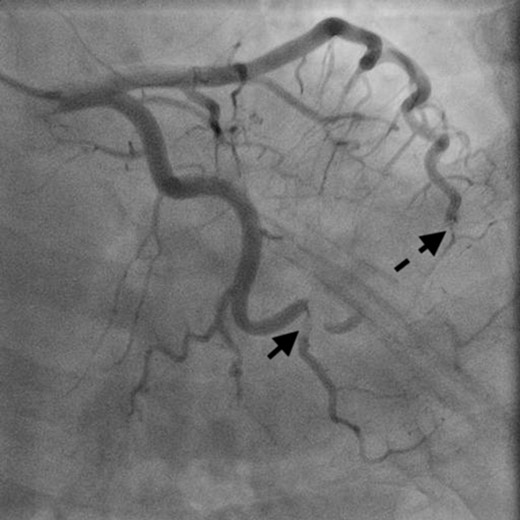

A 46-year-old woman with a history of long-standing SLE and APLS for >17 years and two recent cerebral infarctions was referred to our emergency department with a sudden-onset chest pain and dyspnea (New York Heart Association functional class III). Her usual steroid dose was 10 mg per day. Secondary to SLE associated thrombocytopenia she was anticoagulated with dabigatran. The EKG was consisted with anterior wall STEMI. Troponin level was 1.850. Coronary angiography showed obstruction at the distal left anterior descending and left circumflex arteries (Fig. 1). Transesophageal echocardiography demonstrated a preserved ejection fraction of the left ventricle and a mobile vegetation measuring 9 × 6 mm2 at the mitral valve (Fig. 2). Blood cultures were all negative. She urgently underwent mitral valve replacement through mini right thoracotomy to prevent further thromboembolic events. Cardiopulmonary bypass was undertaken femoral arterial and femoral and internal jugular venous cannulation. We did not perform coronary artery bypass graft because the obstructed arteries were quite distal. We identified a mass at the mitral A2 segment rough zone and two very small lesions at the A3 segment without annular calcification or submitral apparatus disease (Fig. 3). A2 segment was largely affected and shortened; therefore, we decided to not proceed the valve repair. Replacement was performed with a 27/29 mm On-X mechanical prosthesis (Medical Carbon Research Institute, LLC, Austin, TX, USA). Anterior and posterior chordae were spared. Aortic cross clamp time was 242 min and cardiopulmonary bypass time was 289 min. A pathological examination of excised valve leaflets demonstrated a fibrin thrombus without an evidence of microorganisms. The postoperative course was uneventful, and she was discharged 14 days after the surgery. She was followed up for 6 months, and her condition was stable.

Coronary angiography showed obstructed distal left anterior descending artery (dotted arrow) and distal left circumflex artery (solid arrow).